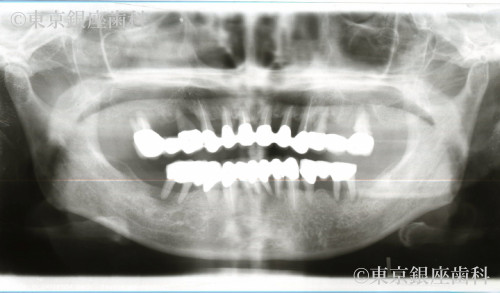

ブリッジ部の歯周病悪化から上下インプラントで噛める機能を回復した60歳代女性の症例

After

上下ブリッジの歯周病悪化・口臭・動揺・痛みに悩んでいたが、下顎から順次インプラントを実施し改善。上下で安定した噛み合わせを獲得。

上下ワンデイインプラント(段階治療)